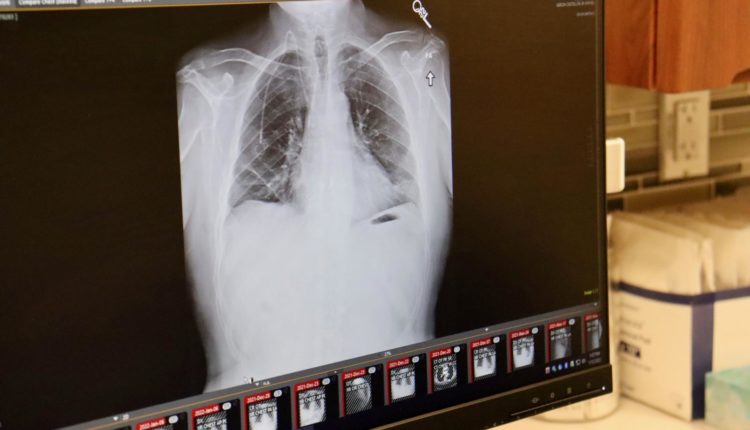

Le patient en question, Albert Khoury, un non fumeur de 54 ans, a passé sept heures sur la table d’opération pour recevoir ses nouveaux poumons, à l’hôpital Northwestern Medicine de Chicago, le 25 septembre 2021.

Six mois plus tard, ses nouveaux poumons fonctionnent bien et il n’a été trouvé aucune trace de cellules cancéreuses dans son corps.